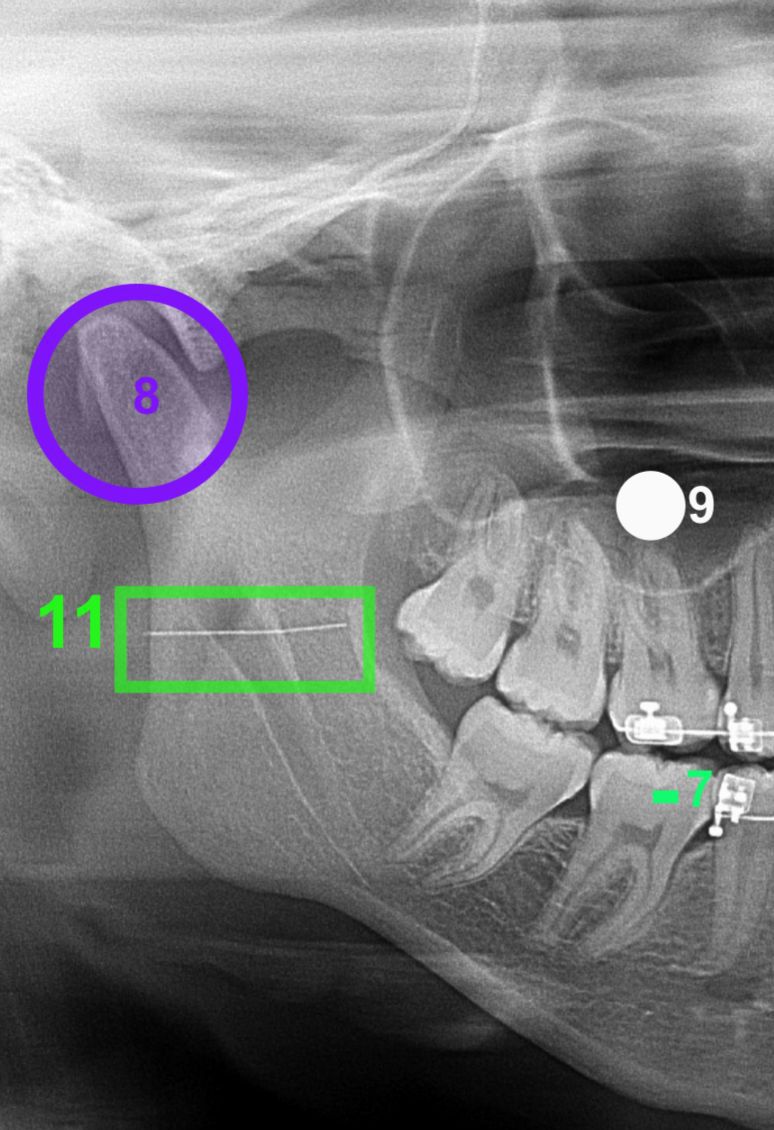

Exames de imagem realizados posteriormente confirmaram a presença do fragmento metálico no ramo mandibular. A criança passou por uma cirurgia em outra unidade especializada, mas o cirurgião responsável concluiu que a retirada do objeto representava risco, já que a profundidade poderia causar danos.

Após o procedimento, a orientação era de que fossem feitos exames trimestrais para monitorar a posição da agulha. Porém, segundo a família, o profissional responsável pelo atendimento inicial não assumiu os custos, obrigando-os a pagar pelos exames em uma clínica de radiologia da cidade.